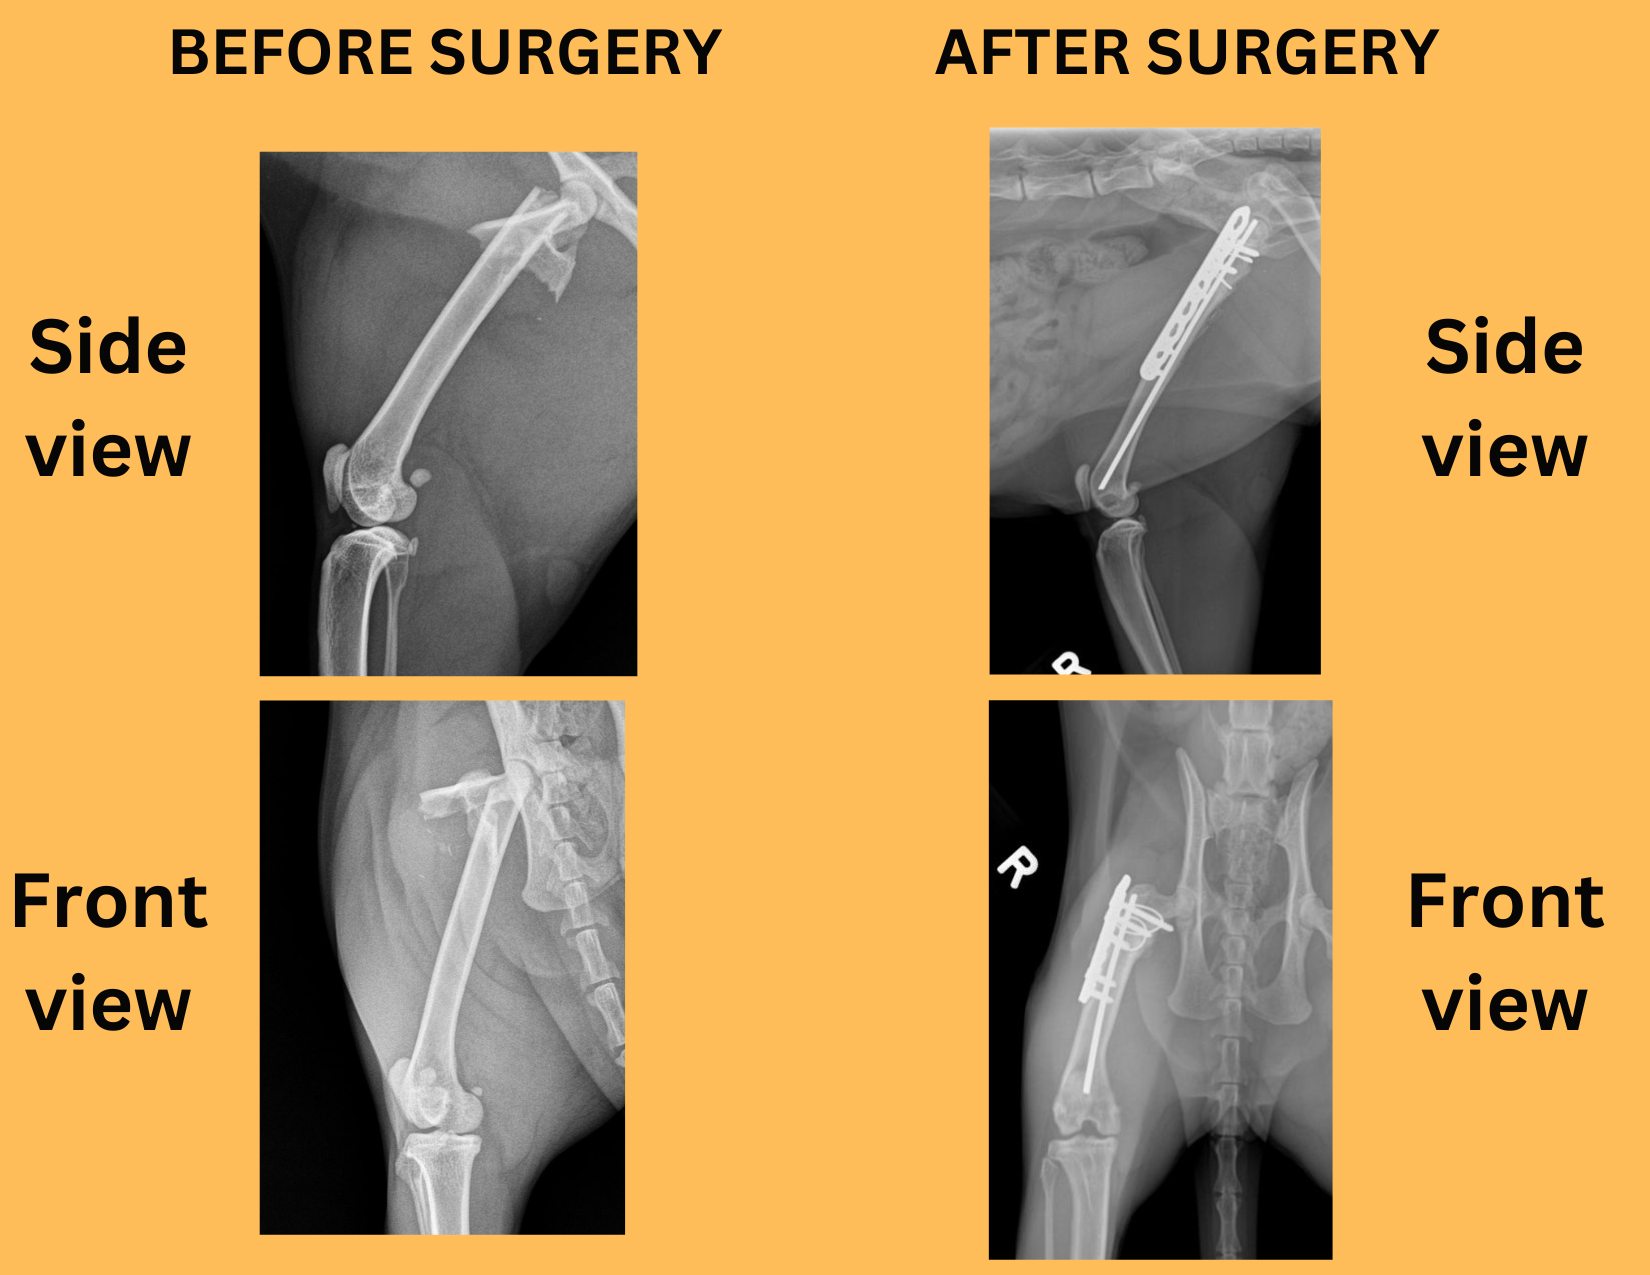

3. Broken bones

We have repaired fractures in virtually every bone: the jaw, the front leg, the pelvis, and the back leg.

Some fractures require a pin, most need a plate and screws.

This is an example of a complex fracture of the thigh bone (femur) that was repaired by Dr. Pete Baia with a pin, a plate and some screws.